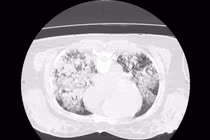

Ngay lập tức, các bác sĩ phải đặt ống nội khí quản và tiến hành hồi sức khẩn cấp. Chụp CT ngực ghi nhận tổn thương lan tỏa hai phổi, phù hợp tình trạng tổn thương phổi cấp sau đuối nước.